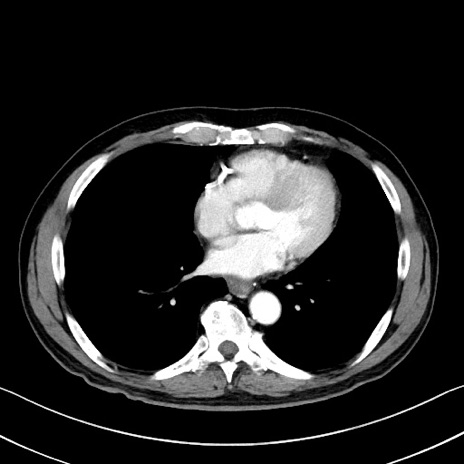

症例35(横断像)

【症例】70歳代 男性

【主訴】腹部膨満、嘔吐

【現病歴】昨日より腹部膨満感出現。本日増悪し、仙痛出現。嘔吐あり、受診。

【既往歴】糖尿病、胆摘後

【身体所見】BP 149/80mmHg、HR 74/min、BT 35.9℃、腹部:膨満、軟、圧痛なし。腸雑音減弱あり。上腹部正中切開瘢痕あり。

【データ】WBC 13500、CRP 1.72